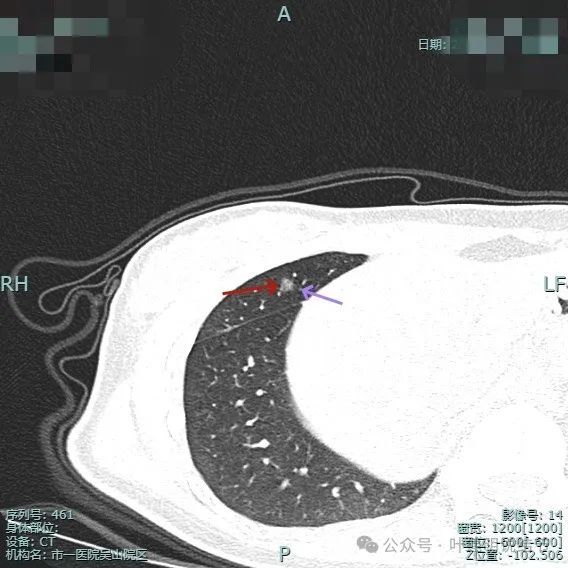

右侧病灶15:

病灶密度仍纯但不太均匀,整体轮廓与瘤肺边界清。

有小血管进入与类反晕征。

血管进入以及轮廓与边界清楚。

密度不均显杂乱。